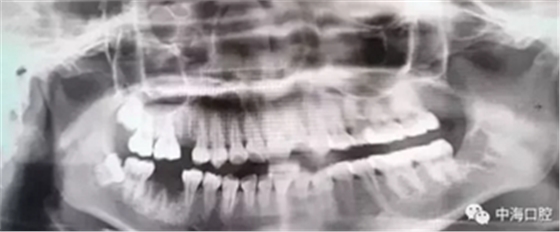

下面這兩張圖,據(jù)說拔牙費(fèi)時(shí)1.5小時(shí),收費(fèi)14000元。